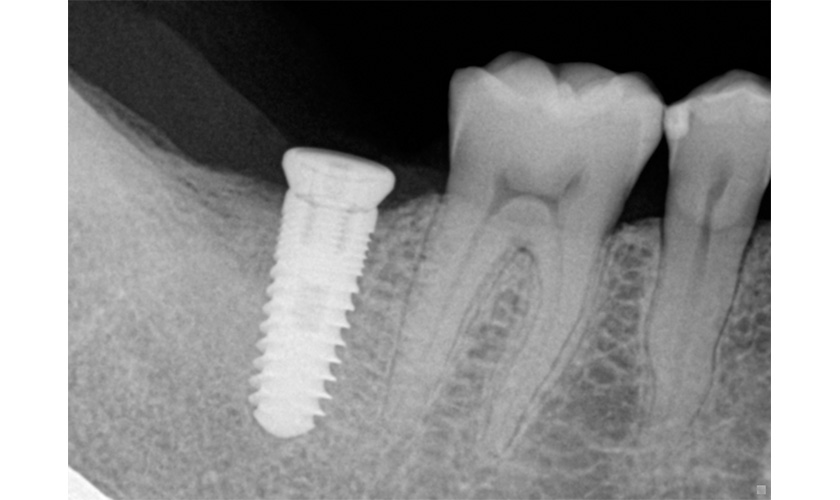

Trụ implant được làm bằng titan và được đặt trực tiếp vào xương hàm để thay thế chân răng đã mất. Sau thời gian lành thương và implant tích hợp vào xương hàm, bác sĩ sẽ tiếp tục chế tạo răng sứ trên implant. Răng trên implant này có chức năng ăn nhai như răng thật vì nó vừa có chân răng nâng đỡ bên dưới vừa có thân răng bên trên.

Titanium đã trở thành chất liệu mở đường cho sự thành công của cấy ghép răng Implant. Năm 1965 ông đã thực hiện ca cấy ghép răng Implant đầu tiên bằng cách sử dụng trụ Titanium tại Thụy Điển và thành công rực rỡ.